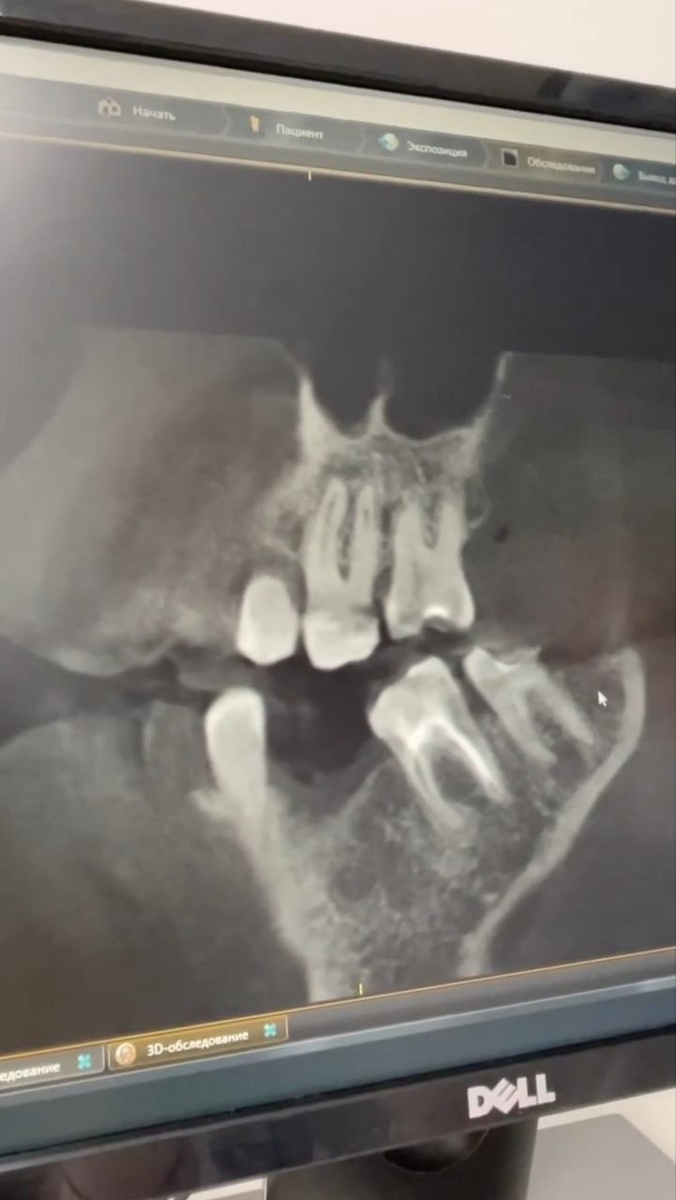

В клиниках ПРАЙМ пациент сначала проходит КЛКТ-диагностику, после которой врач принимает решение, какой метод лечения лучше выбрать.

Чаще всего это апикиальная хирургия (частичное удаление инфицированной верхушки корня зуба) или повторное эндодонтическое вмешательство, т.е. перелечивание каналов зуба с помощью микроскопа.